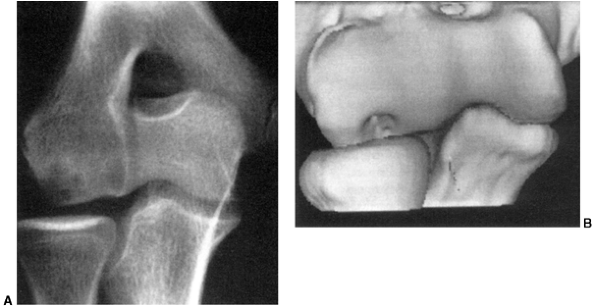

![]() |

|

Figure 32.21 A: Magnetic resonance image (MRI) of a knee demonstrating osteochondritis dissecans lesion (black arrows)

in the classical location (lateral aspect of medial femoral condyle). The lesion appears to be stable, with an intact articular surface. B: Lateral image of same knee (black arrows outline lesion). |